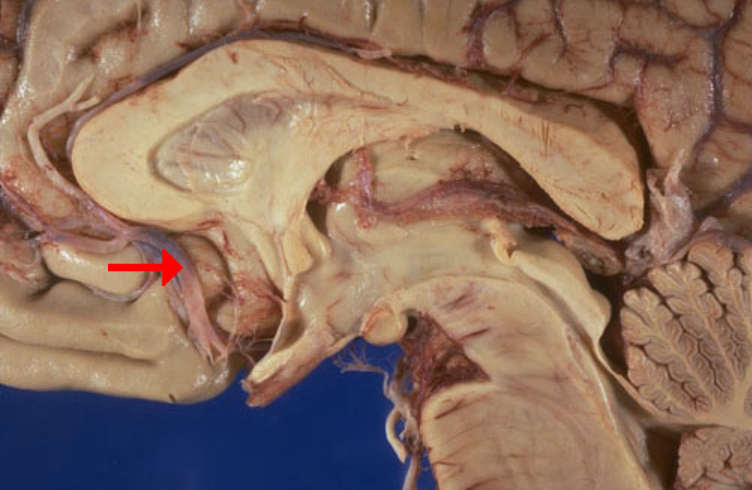

Label this structure

Hypoglossal (CN XII) nerve